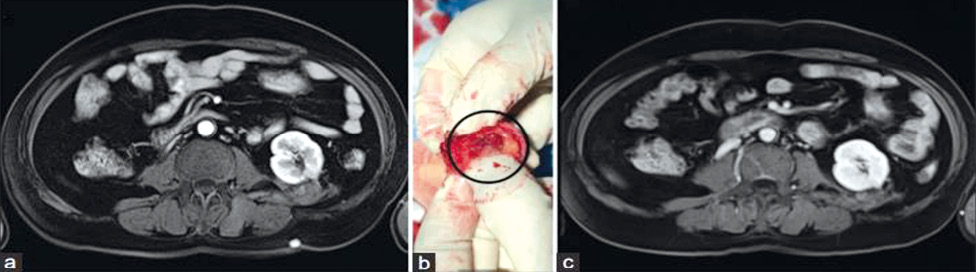

У проведеному ретроспективному аналізі даних 45 історій хвороб пацієнтів, яким у період 2018–2022 рр. виконано фокальну терапію раку передміхурової залози з використанням НОЕ [4]. Встановлено, що метод зумовив хороші онкологічні результати як у випадку первинної терапії (N-38), так і у вигляді терапії порятунку після неефективної дистанційної променевої терапії або брахітерапії та андроген-деприваційної терапії (АДТ) (N-7) (рис. 1).

Рис. 1. Проведення процедури НОЕ (NanoKnife): a) — електроди, введені через сітку для промежинної біопсії, паралельно до ультразвукового датчика; b) — пацієнт з групи первинного лікування. Ультразвукове поперечне зображення, зеленим кольором позначено контур передміхурової залози, червоним — ділянку ураження. T — пухлина; E — електрод (1–4); C — катетер. Пухлина оточена безпечним краєм; c) — пацієнт з групи терапії порятунку після невдалої брахітерапії. Справа ураження (червоне) і передміхурова залоза (зелена) в 3D-вигляді (Bio-Jet, Fusion system, BK ultrasound). Поперечний вигляд; T — пухлина; E — електрод (1–4); BS — насінини для брахітерапії. Ураження знаходиться справа постеролатерально в Mid-сегменті передміхурової залози. Електроди оточують ураження, з урахуванням безпечного краю [цит. за 2]